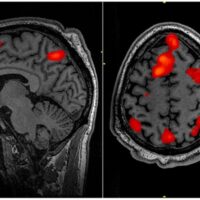

Depressed individuals who reflexively attempt to dampen their initial emotional responses to reminders of their negative memories have a low tolerance for distressing emotional stimuli in general and may …